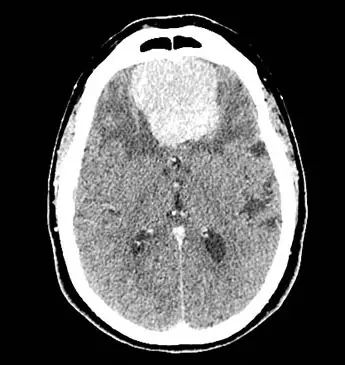

脑膜瘤是较常见的良性颅内肿瘤,占全部颅内肿瘤的三分之一以上,尸检时发现,2.3%的患者存在脑膜瘤。由于计算机断层扫描(CT)和核磁共振成像(MRI)利用增多,因此无症状脑膜瘤得以检出,估计多达2/5的脑膜瘤患者没有症状。下图的CT增强扫描显示一例77岁老年女性前颅底内前壁内均匀强化肿物。患者出现嗅觉丧失和进行性人格改变,包括其正常社会生活中的控制力丧失和兴趣下降。后对患者行简单的开颅手术,进行了肿瘤全切除;病理显示病变为国际卫生组织(WHO)分级I级脑膜瘤。